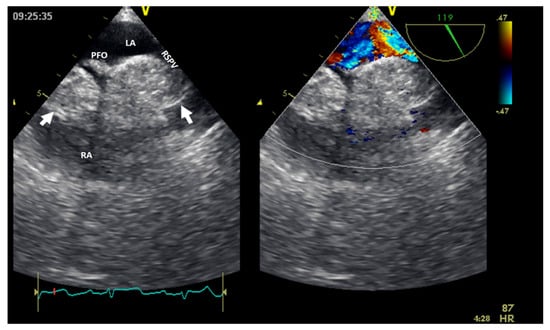

Echocardiography with ultrasound-enhancing agents is the best modality for tissue characterization [13]. Two-dimensional TTE may sometimes overrate the size of myxomas or very soft tumors (myxoid- or gelatinous-type masses) due to their distensibility, mobility, or irregular shape, especially when compared to three-dimensional TEE. However, the size of the tumor is appropriately assessed by TTE in most cases. The site and type of tumor attachment, a useful clue to define the type of cardiac tumor, could be determined easily by TEE (especially 3D). For example, right atrium angiosarcomas, described as heterogenic masses with central necrosis on CT or CMR [13], could be attached to any part of the right atrial wall, while myxomas (Figure 2) are usually situated in the fossa ovalis region of the atrial septum (most frequently on the left side).

Figure 2.

Two−dimensional transesophageal echocardiography (short-axis view at the level of the great vessels) showing a huge inhomogeneous mass (arrow) attached to the interatrial septum crossing the tricuspid valve (which, upon histology diagnosis, was a myxoma). AO, aorta; IAS, interatrial septum; LA, left atrium; RA, right atrium; RV, right ventricle.

Figure 7.

Two−dimensional transesophageal echocardiography with color Doppler (high transesophageal view at 119°) showing two tumors (arrow) at the level of the interatrial septum with compression on the right superior pulmonary vein (right image). LA, left atrium; LV, left ventricle; PFO, permeable foramen oval; RA, right atrium; RSPV, right superior pulmonary vein.